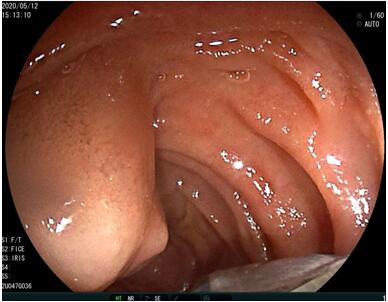

69歲王姓患者,因“發(fā)現(xiàn)無痛性黃疸1月”入院���,根據(jù)患者病史���,患者診斷傾向于壺腹部腫瘤所致梗阻性黃疸。予以完善腹部CT及上腹部MRI加MRCP均顯示肝內(nèi)外膽管擴張�,未發(fā)現(xiàn)明顯膽管,胰腺及十二指腸乳頭部腫瘤�����,且患者CA199正常����。以前醫(yī)院未引進超聲內(nèi)鏡��,這類患者到此就遇到診斷瓶頸�����。此患者經(jīng)過消化內(nèi)科張丹霞副主任醫(yī)師完善超聲內(nèi)鏡檢查后����,可以清楚顯示膽總管下段壁內(nèi)軟組織占位�����?����;颊咄ㄟ^超聲內(nèi)鏡檢查診斷明確�,轉(zhuǎn)至肝膽外科行手術(shù)治療。

超聲胃鏡圖片

膽總管小腫瘤性病變CT及MRI檢查陽性率偏低�����,因其低代謝特征,PET-CT陽性率也偏低���,超聲內(nèi)鏡對這類疾病的診斷陽性率是所有檢查中最高的,且可行穿刺活檢進一步確診病灶性質(zhì)��。

環(huán)掃超聲內(nèi)鏡主要用于胃腸道粘膜下腫物診斷���,胃腸道腫瘤分期�����,發(fā)現(xiàn)早期胃癌等��,扇掃超聲內(nèi)鏡主要用于診斷膽道及胰腺疾病����,并且可行穿刺活檢取病理���。